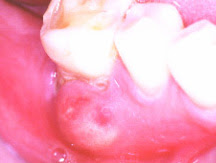

The most common cause of an abscess in your mouth is a bacterial infection.

It could be on your gums or anywhere in your mouth. It is important to learn how to get rid of an abscess in your mouth as early as possible to avoid further complications. A gum abscess occurs when bacteria in the mouth causes an infection in the space between the teeth and the gums. Some gum abscesses result from periodontitis disease, which is caused by poor oral. Another antibiotic that is also recommended by the BNF is co-amoxiclav,.